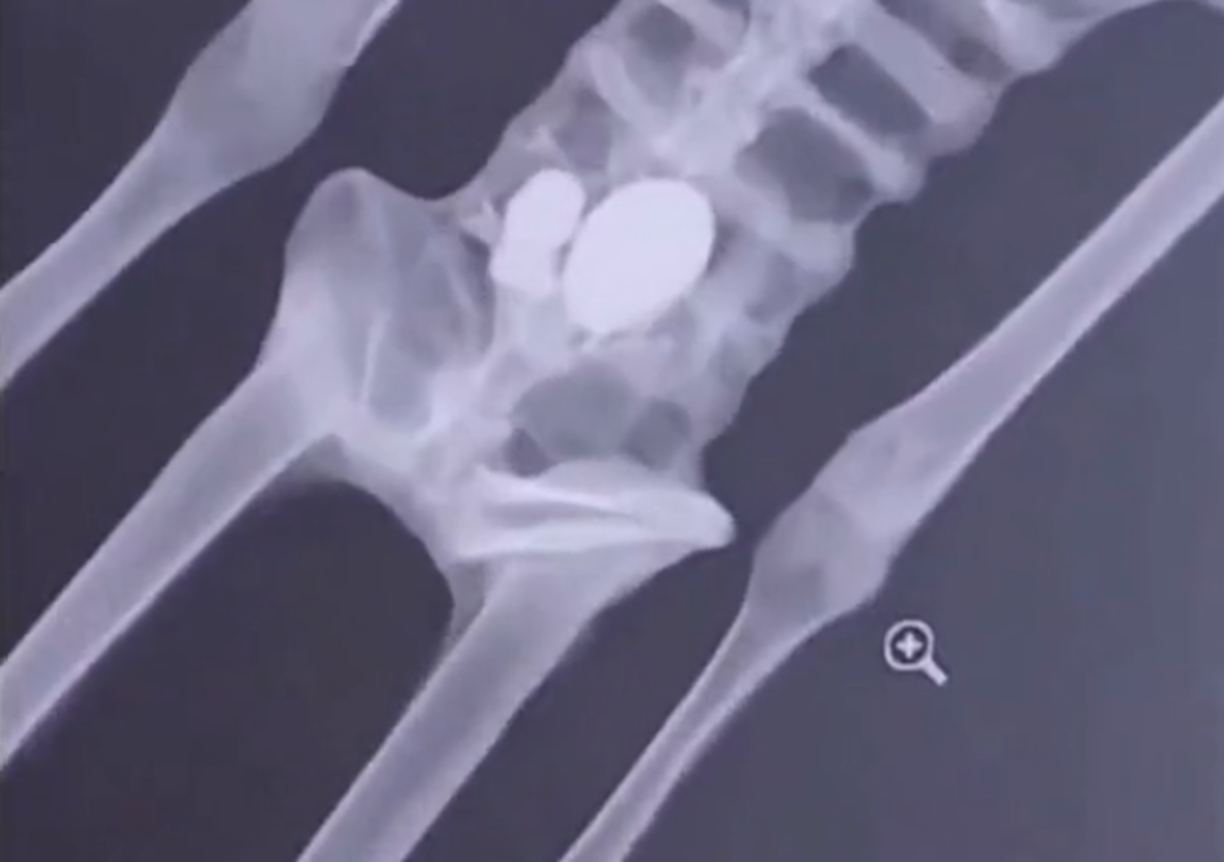

1 / 16Con la muestra de dos cuerpos de seres no humanos en la cámara de Diputados de México, el ufólogo Jaime Maussan y expertos en la materia pidieron a los legisladores reconocer la vida extraterrestre en el país.

3 / 16El ufólogo y comunicador mexicano presumió que los dos cuerpos mostrados tenían más de 1.000 años, de acuerdo con una investigación realizada por la Universidad Nacional Autónoma de México (UNAM).

4 / 16Institución que determinó, mediante análisis de carbono 14, que se mantuvieron sepultados por un milenio dentro de una diatomea, un tipo de alga que no permite el crecimiento de bacterias ni de hongos, lo que permitió su preservación.

6 / 16“No se trata de momias, se trata de cuerpos que están íntegros, completos, que no han sido manipulados en su interior y que tienen una serie de elementos que los hacen verdaderamente extraordinarios”, expresó.